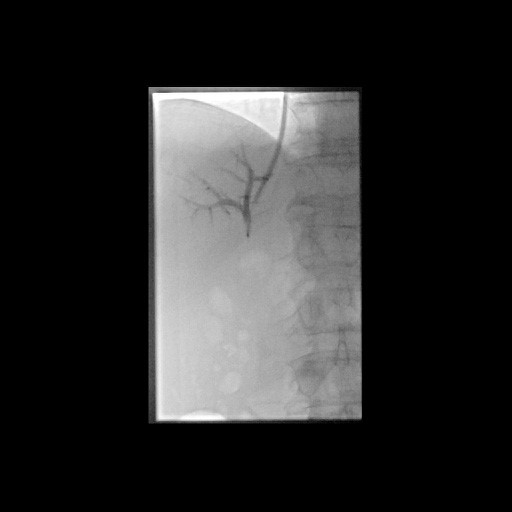

Postoperative abdominelle Blutungen bei chronischer Pankreatitis vor Embolisation der Art. gastroduodenalis mittels Metallspiralen (Coils)

(Bild 2 von 5)